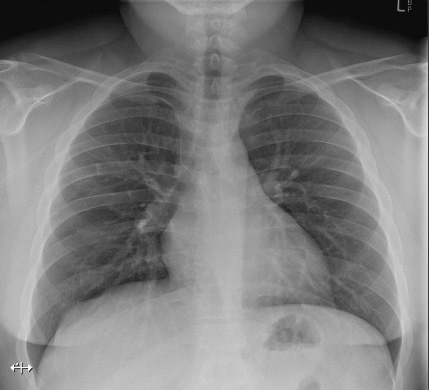

20.2 A patient has a peripherally inserted central catheter (PICC) inserted. The follow-up chest X-ray shows the tip positioned in the (Chest X-Ray shown)

a) Azygos vein

b) Coronary sinus

c) SVC

d) R atrium

e) L atrium

Correct positioning in image